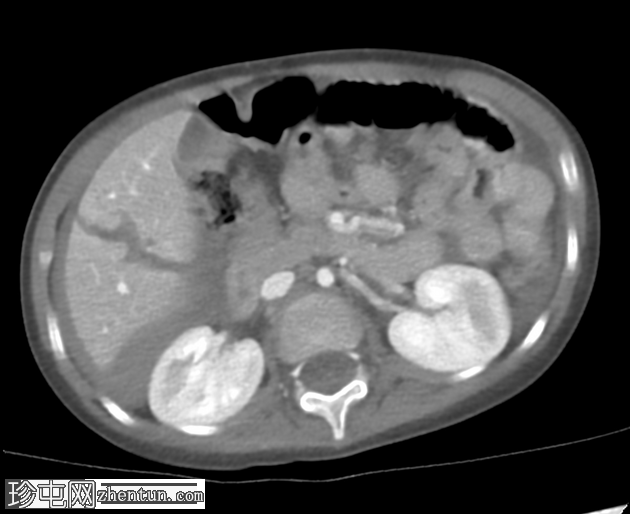

轴向C+门静脉期

AAST IV级肝撕裂伤,伴有大面积不规则肝损伤,累及V段(轴向、冠状、矢状)。

撕裂伤区域内未见活动性造影剂外渗。

可见中等量腹腔积血。